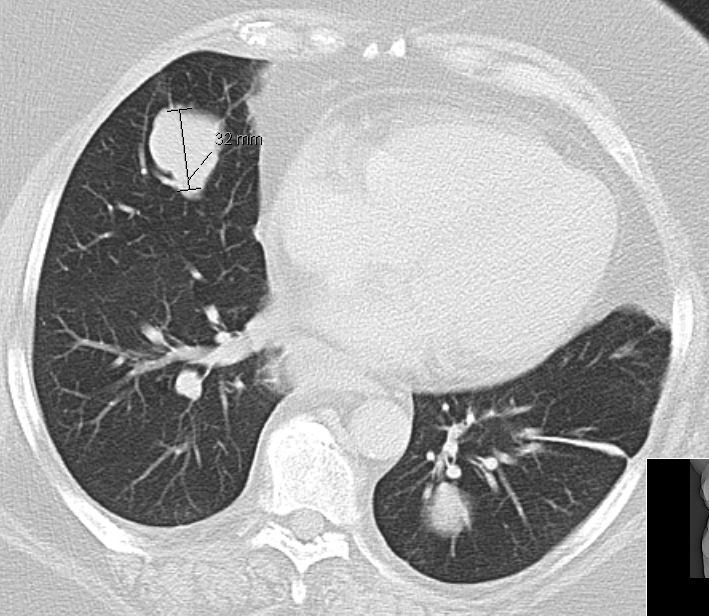

| Lunge | 58-jährige Frau, die vor 3,5 Jahren ein

Endometriumkarzinom pT2 pNo(0/33) Mo G1 hatte. 10 Monate später Pleuraerguss,

pulmonale Metastasen. Jetzt 3. Progress Carboplatin, Taxol, MPA.![]() |

![]() |